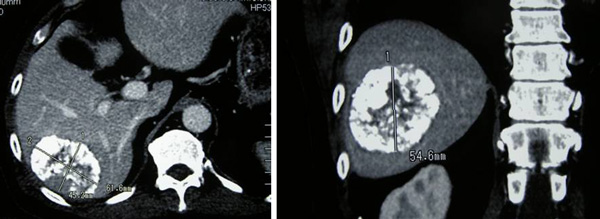

On 6 April 2011, a CT scan was performed. The previously treated mass in the right lobe of his liver measures approximately 3.5 x 5.1 x 4.8 cm in size. There is no associated hypervascularity seen with this mass. However, there is a new lesion in segment 5 of the right lobe of his liver. It is 3.1 x 2.3 x 3.6 in size.  This mass was not present on the previous scan of October 2010 and is suspicious of recurrent disease.

1. There is a 5.1 x 4.2 x 4.8 cm mass in segment 6 of the liver.

2. There is a 2.7 x 2.8 x 3.3 cm enhancing lesion in segment 5 of the liver.

3. There is an ill-defined enhancing lesion measuring about 2.3 cm in segment 8 of the liver.

4. There is a 2.5 x 2 x 2.1 cm mass just inferior to the right adrenal gland. Metastasis?

5. There is a 1.9 x 1.6 x 2.5 cm mass just inferior to the left adrenal gland. Metastasis?

6. There is a lytic lesion in the vertebral body of T12. Fracture of the superior endplate of T12 is noted. This probably represents a bony metastasis.

On 13 August 2011, MRI of the thoracic spine was carried out. The result confirmed a lesion measuring 3.5 x2.4 x 2.2 cm in T12 vertebra. The mass extends into the spinal canal and displacing the nerve roots. Findings are in keeping with a metastatic lesion.